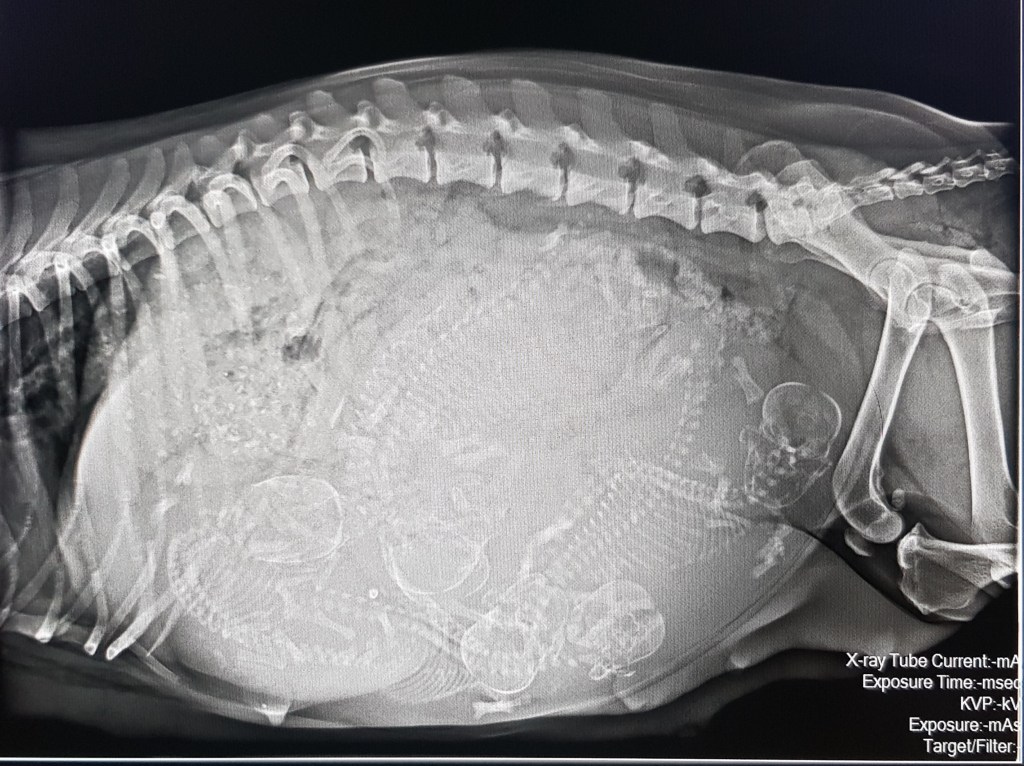

Heute waren wir mit Claire beim Röntgencheck und freuen uns auf die bevorstehende Geburt …

G-Wurf